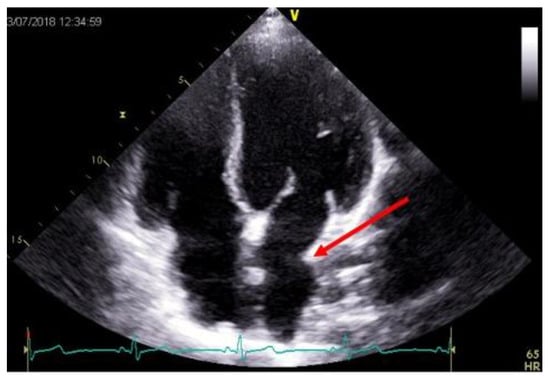

5. Role of Echocardiography in the Evaluation of Cardiac Allograft Vasculopathy

- Sciaccaluga, C.; Ghionzoli, N.; Mandoli, G.; Sisti, N.; D’Ascenzi, F.; Focardi, M.; Bernazzali, S.; Vergaro, G.; Emdin, M.; Valente, S.; et al. The role of non-invasive imaging modalities in cardiac allograft vasculopathy: An updated focus on current evidences. Heart Fail. Rev. 2021, 1–12. [Google Scholar] [CrossRef] [PubMed]

- Clemmensen, T.S.; Løgstrup, B.B.; Eiskjær, H.; Poulsen, S.H. Evaluation of longitudinal myocardial deformation by 2-dimensional speckle-tracking echocardiography in heart transplant recipients: Relation to coronary allograft vasculopathy. J. Heart Lung Transplant. 2015, 34, 195–203. [Google Scholar] [CrossRef] [PubMed]

- Dandel, M.; Hetzer, R. Post-transplant surveillance for acute rejection and allograft vasculopathy by echocardiography: Use-fulness of myocardial velocity and deformation imaging. J. Heart Lung Transplant. 2017, 36, 117–131. [Google Scholar] [CrossRef]

- Sciaccaluga, C.; Mandoli, G.E.; Sisti, N.; Natali, M.B.; Ibrahim, A.; Menci, D.; D’Errico, A.; Donati, G.; Benfari, G.; Valente, S.; et al. Detection of cardiac allograft vasculopathy by multi-layer left ventricular longitudinal strain in heart transplant recipients. Int. J. Cardiovasc. Imaging 2021, 37, 1621–1628. [Google Scholar] [CrossRef]